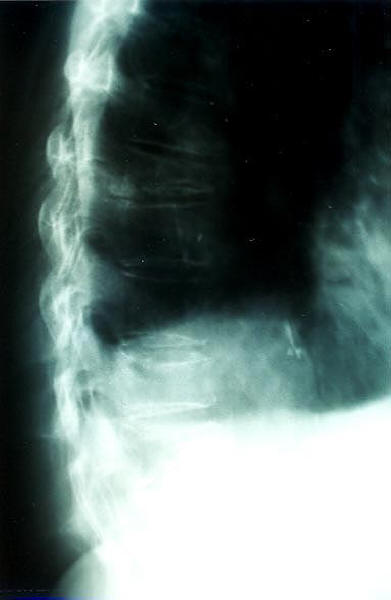

Osteoporosis. Cifosis.